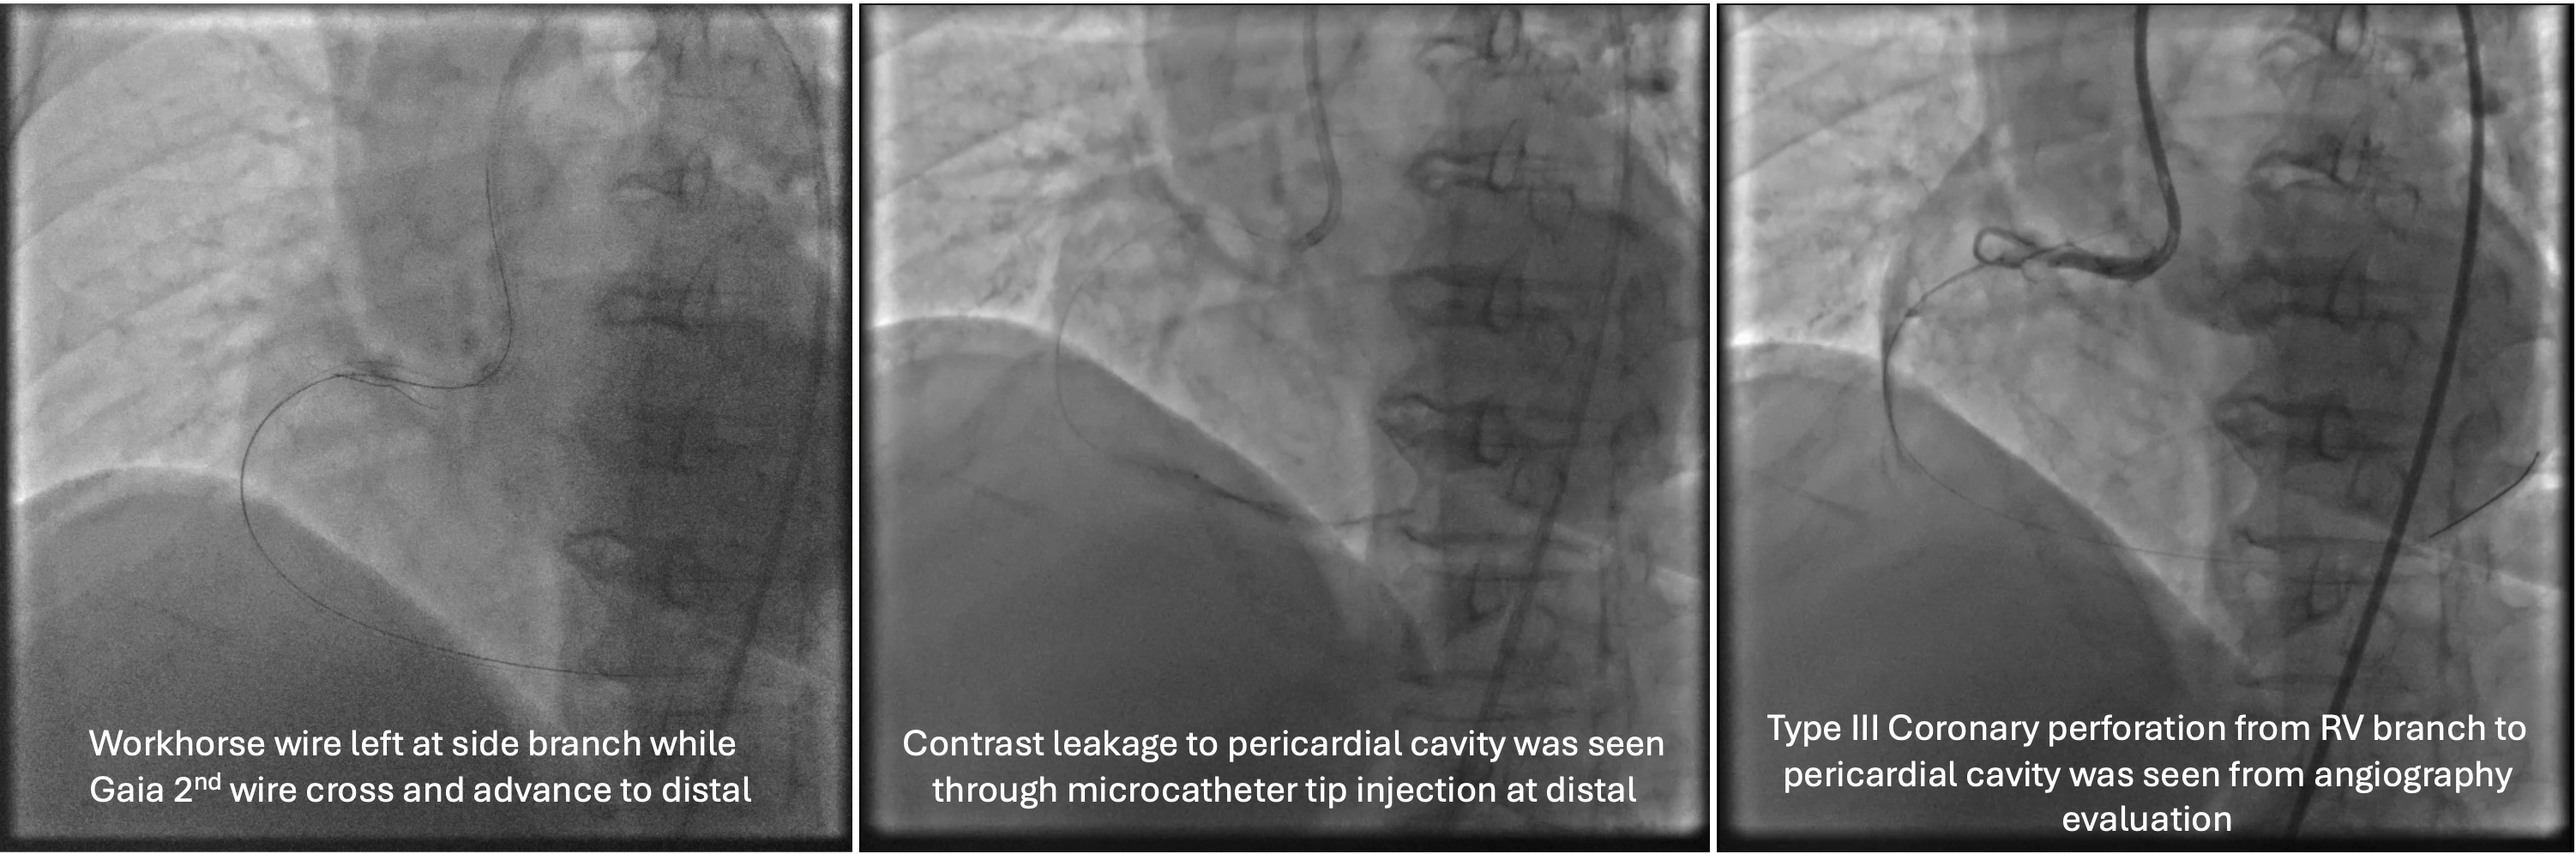

Several attempts to cross the lesion with workhorse wire and polymer jacketed wire with microcatheter support were failed because the wire went into small branch proximal to the occlusion. Guide catheter AL 0.75/7F was exchanged for JR 3.5/7F because of frequent pressure damping associated with deep engagement. Workhorse wire was left at the small branch while the second stiff wire was attempted to cross. The stiff wire (Gaia 2nd wire) and microcatheter was successfully cross and advanced to the distal. Microcatheter tip injection revealed contrast leakage to pericardial cavity. The stiff wire was exchanged for less traumatic workhorse wire and microcatheter was left to tampon the coronary perforation. Due to vague course of the vessel, rewiring to RCA was done with polymer jacketed wire in knuckle technique that eventually succeeded to cross the lesion and enter the true lumen. Pre-dilatation with semi-compliant balloon 2.5x15 mm at proximal-mid RCA was done to restore the flow. Angiography revealed tortuous and calcified RCA with some contrast leakage confined to pericardium. Subcutaneous fat embolization was attempted several times to seal the perforation. With minimal residual leakage, pre-dilatation with non-compliant balloon 3.0x18 mm was proceeded. Stent DES 3.0x38 mm was implanted at the proximal-mid RCA with the aid of 6F guide extension catheter. Angiography evaluation demonstrated good PCI result leaving only minimal residual contrast leakage confined to pericardium.